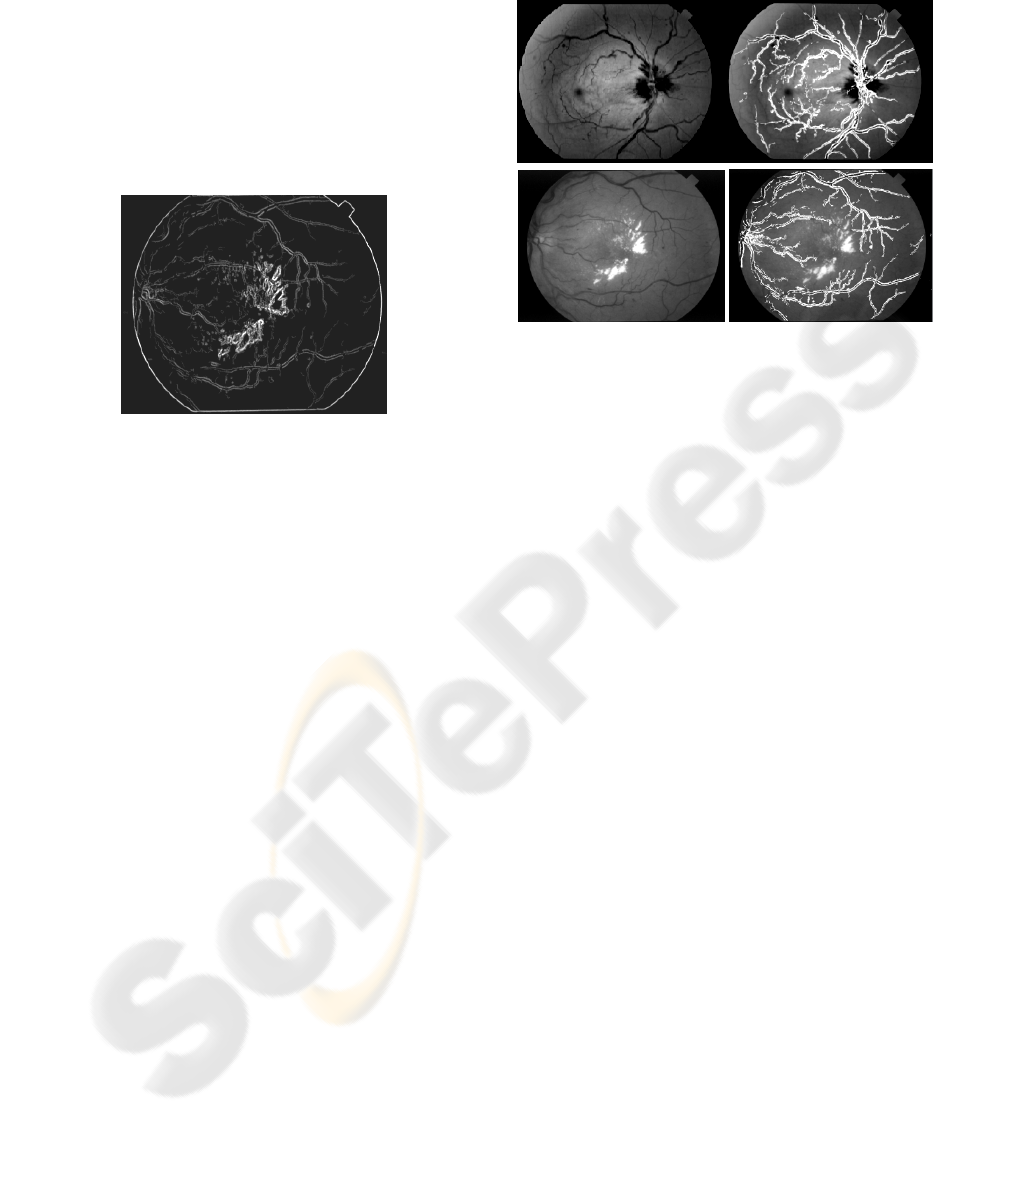

mapping the original retinal images. Figure 5 below

displays two examples of images from the dataset

and their output.

Figure 5: Original retinal image (left) and detected vessels

(right).

Figure 5 shows two example images and the output

after blood vessel segmentation using the proposed

method. The first retinal image is almost a normal

eye and we observe that 99% vessels are detected

properly. However, the second retinal image suffers

from noise and the detection rate falls to

approximately 90%. This fall in detection rate is due

to the fact that if any part of the retinal image suffers

from noise like block (eg. haemorrhage) then the

whole area is removed as we consider only the

parallel regions. Therefore, it is possible to miss

vessels from that particular part of the retinal image.